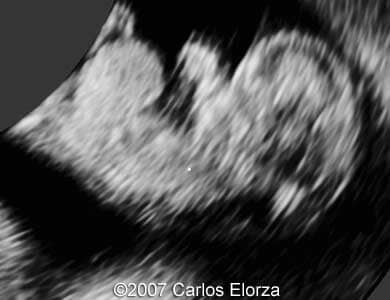

38-year-old woman (G3, P2)Ā presented in our department at 10th week of pregnancy. Ultrasound examination discovered striking nuchal edema and omphalocele with liver"s exenteration. A chorionic biopsy revealed trisomy 13. Here are someĀ images that we obtained.